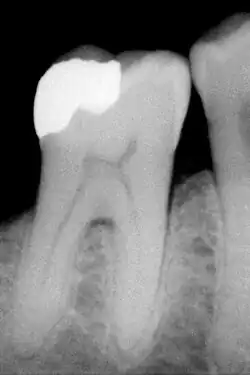

Amalgaam in de tandheelkunde

Moderne tandheelkundige amalgamen worden uit twee componenten gemaakt: een poeder van een verbinding van tin en zilver, samen en meer dan 50% kwik, de vloeistof. Bij het mengen, het tritureren, komt het kwik in contact met de poederdeeltjes en gaan de deeltjes oplossen. Aldus ontstaat een matrix van zilver-kwik- en tin-kwikdeeltjes, met een vulstof van de niet-aangetaste zilver-tindeeltjes.

- Amalgaam hecht niet aan het dentine, dat is het tandbeen, en aan glazuur, waardoor het gaatje extra moet worden uitgeboord om de vulling mechanisch vast te zetten. De vulling krijgt dan op doorsnee een wigvorm. Zeker bij zeer grote amalgaamvullingen kunnen er zich na enige tijd breuken van de omringende glazuurwanden voordoen. Meestal zijn dit glazuurbreuken, een enkele maal ook een gecompliceerde breuk tot onder het tandvlees of tot op de zenuw.